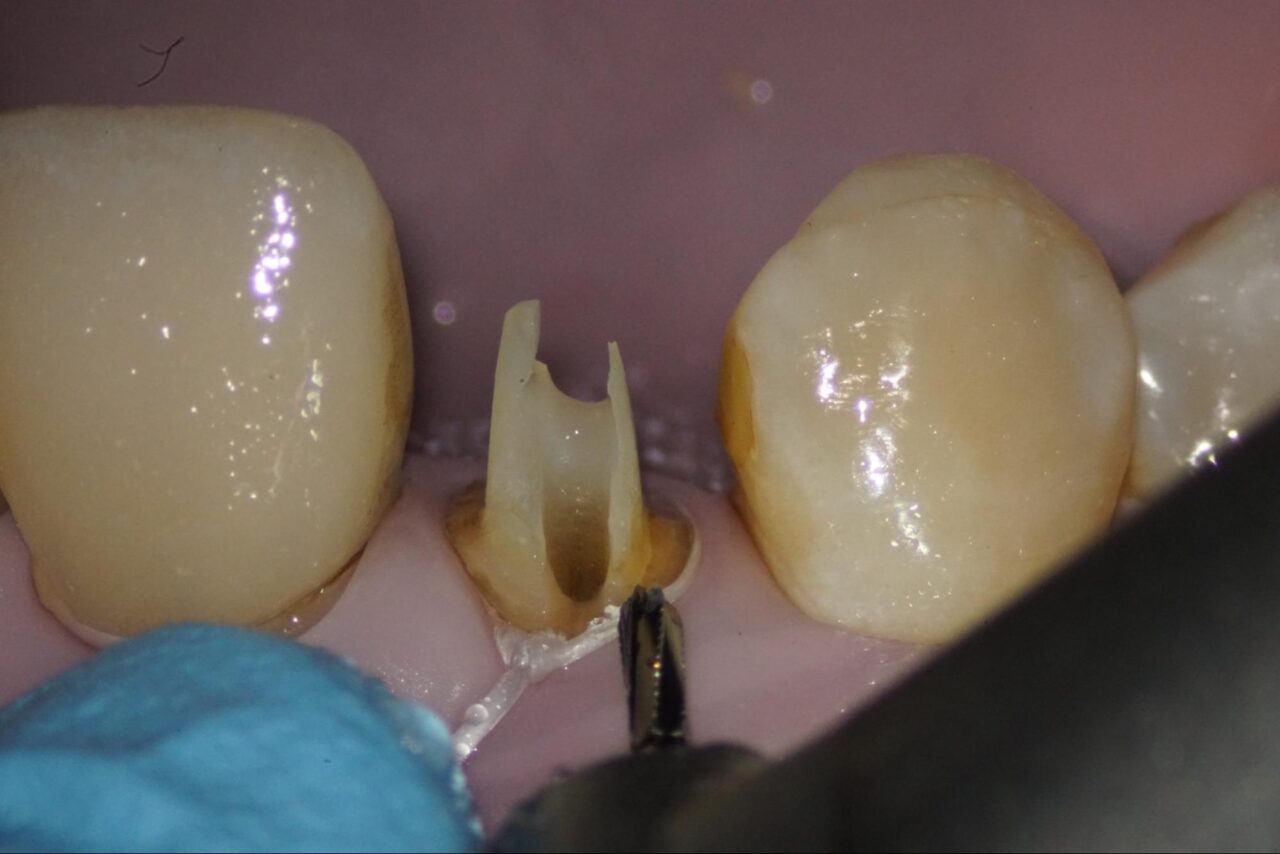

感染部がグリーンに染まるカリエスディテクターを用いながら削っていくと頰側にクラックが入っている事が確認できます。

標準的な診断では、この時点で根管治療は終了となり、抜歯になりますが、吉松歯科医院では接着技術を用いて、可能な限り自分の歯を残すための治療を行なっています。

以前の根管充填材を取り除いて行きます。

以前の根管充填材は、感染部質なので完全に取り除く必要があります。この写真では根尖部にまだ残っている事が確認できます。